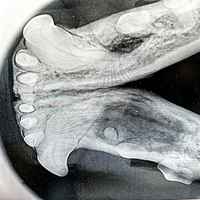

Eine umfassende und tiefgreifende Diagnostik ist auch in der Tiermedizin das A und O des Heilungserfolges. Nicht immer genügt eine allgemeine klinische Untersuchung, ein Tier zu begutachten, um eine eindeutige Diagnose zu stellen. Manche Symptome lassen kein eindeutiges Urteil zu, so dass wir in diesen Fällen auf bildgebende Verfahren wie Sonografie und digitales Röntgen zurückgreifen. So können Diagnosen schnell, konkret und direkt vor Ort in unserer Praxis erstellt werden.

- Digitales Röntgen